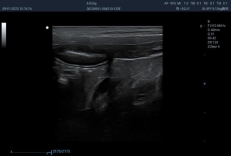

10L2PD ● 4.2-16.0MHz ● High-frequency linear array probe ● For Abdomen and Small Parts |

![]() |